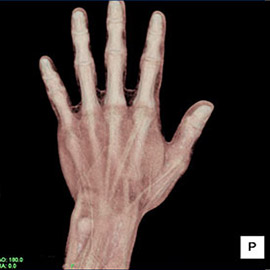

80列マルチスライスCT 検査 画像例

80列マルチスライスCTで撮影した画像

整形